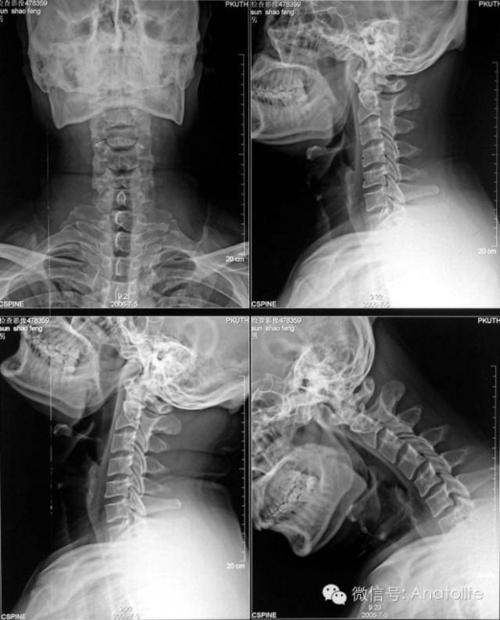

颈椎正侧位如何备孕

在备孕的时候,女性可以去医院检查一下颈椎情况,如果有不适,要尽早治疗。如果颈椎疼痛,可以用热水热敷。或者试着用枕头垫高30度,让颈椎保持90度左右的状态,这个是很有利于备孕的。但是备孕期间是不能有太大的动作,因为这个时候女性的身体还没有完全的康复,很容易受到外界的影响,所以,如果颈椎疼痛,很可能会影响到宝宝的发育。

当颈椎问题比较严重的时候,不管是备孕还是缓解,如果症状比较严重,建议到医院进行治疗,以免耽误自己的病情,对备孕造成影响。女性要调整好自己的作息时间,对于颈椎疾病有好处。备孕期间女性可以做一些简单的锻炼,比如慢走,瑜伽,游泳都是很不错的选择。但是不能做一些不利于身体健康的运动,比如抬头、竖头等。